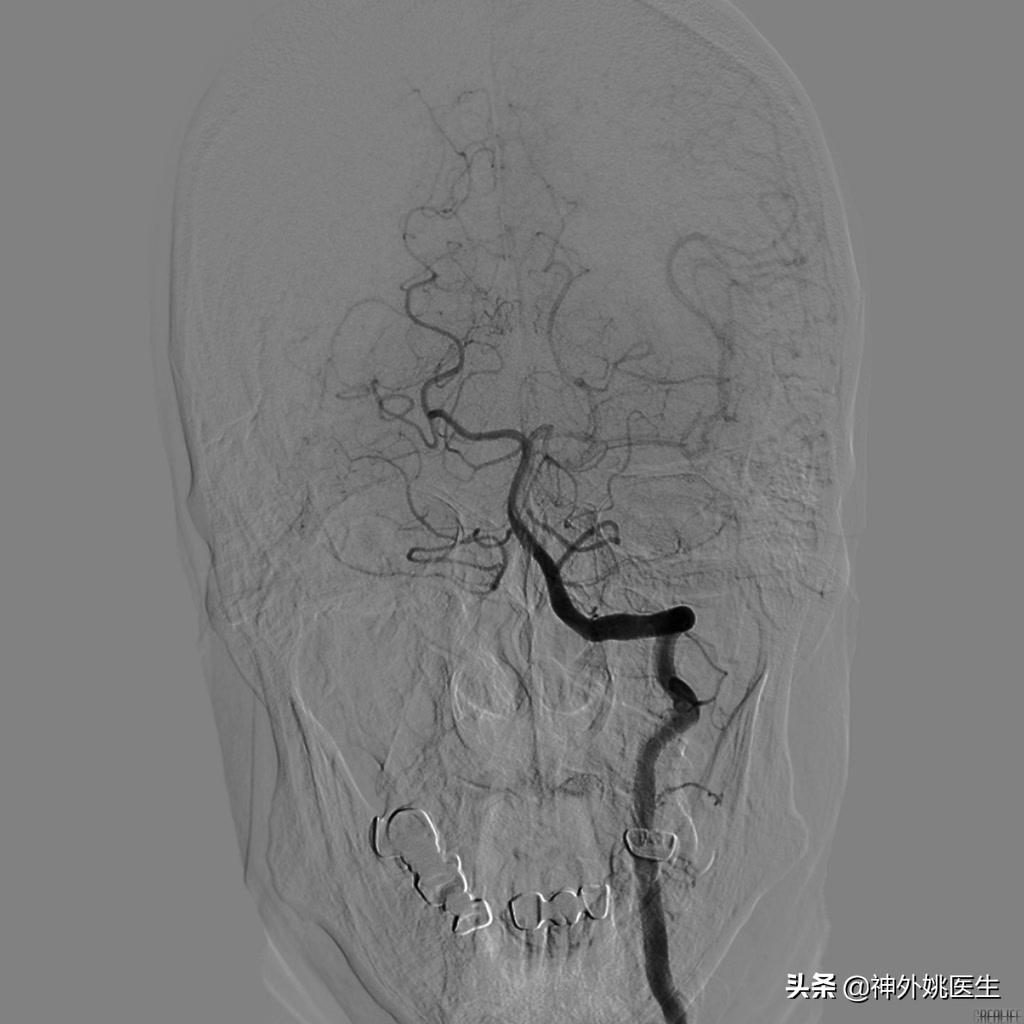

术前DSA检查:(图3-6)

图4 右颈动脉造影示前交通动脉开放,左侧A2以远显影,通过左侧A1至M1以远亦显影。

图5 左侧颈动脉造影示左侧大脑前动脉显影欠佳。

图6 椎基底动脉造影示左侧后交通动脉开放,左侧大脑中动脉显影。